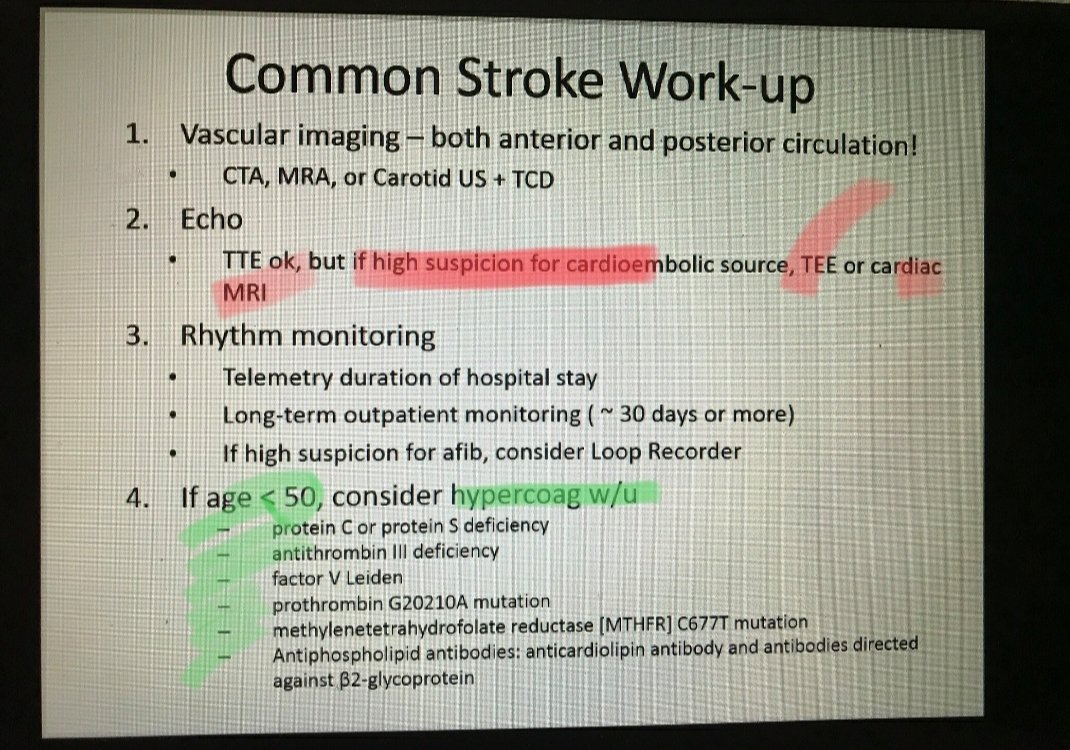

#السكته_الدماغيه_الاقفاريه

💥الفحوصات الاساسيه

🧠اشعه مقطعيه/رنين للمخ

🧠دراسه الشرايين المغذيه للمخ

تختار حسب مكان الجلطه/وظائف الكلى/التوفر

(مقطعيه بالصبغه/رنين مغناطيسي/اشعه صوتيه للرقبه/قسطرة تداخليه)

🧠فحوصات للقلب

♦️تخطيط عادي/مطول

♦️اشعه صوتيهECHOمباشرة/بمنظار

#السكته_الدماغيه_الاقفاريه

💥تابع الفحوصات

🧠تحاليل دم

♦️صورة خلايا الدمCBC

♦️سيوله الدم

♦️السكر التراكمي

♦️الكوليسترول الضار

♦️وظائف الكلى

💥تحاليل اضافيه قد نحتاجها

🧠تحاليل زيادة تجلط الدم

🧠بحث عن أورام مختبئه

🧠أمراض جينيه/وراثيه

🧠أمراض مناعيه

🧠سموم

🧠اخذ خزعه من الظهر